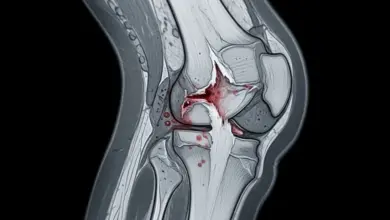

O entesófito é uma formação óssea que surge no ponto de fixação de tendões ou ligamentos no osso, que pode aparecer como resposta a tração repetitiva, desgaste progressivo, inflamação crônica ou alterações mecânicas do joelho.

O entesófito é uma projeção óssea formada na entese, que é o local onde tendões, ligamentos ou cápsula articular se prendem ao osso. No joelho, pode acontecer em regiões como:

Esse achado pode estar ligado ao envelhecimento articular, a processos inflamatórios de longa duração, à tração excessiva do aparelho extensor e até a alterações de alinhamento do membro inferior.

Em alguns pacientes, ele é apenas um sinal radiográfico. Em outros, participa do quadro doloroso de forma direta.